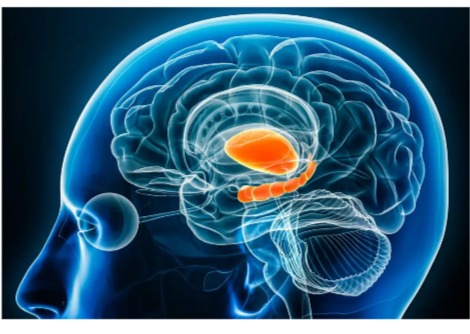

اكتشاف الروابط الدماغية المفقودة التي قد تكون وراء التسبب بالهلوسة عند مصابي مرض باركنسون